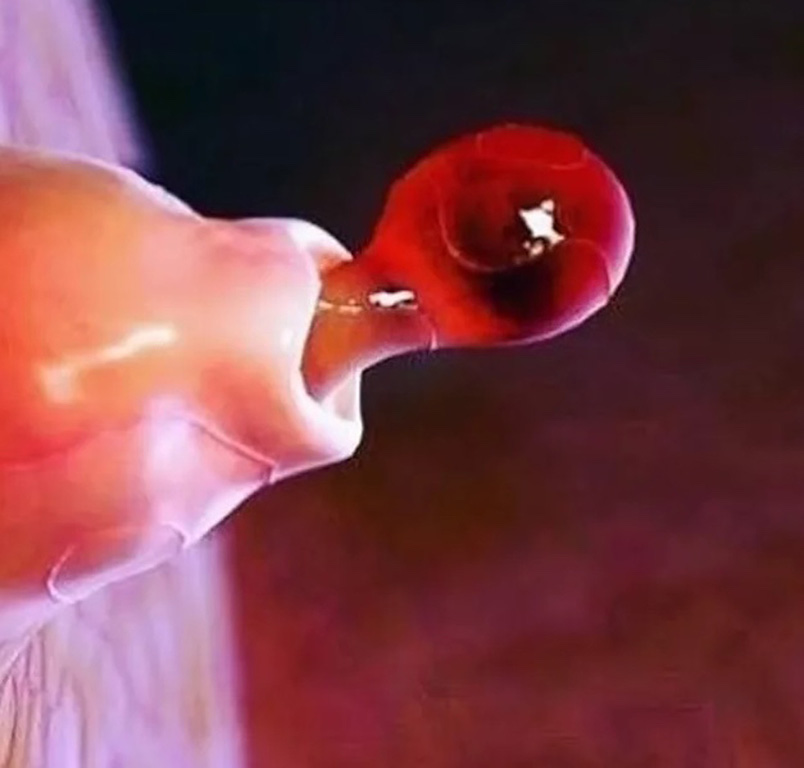

Primer punto, el alto grado de detalle que tienen las fotos. Se nos dificulta concebir un ojo, un óvulo, un pulmón, el iris del ojo, la célula capilar del oído, como unidades separadas y no como partes de un todo.

La representación del iris del ojo no tiene nada que ver con el placer que sentimos cuando (a través de ese iris) observamos algo bello. La representación de la superficie de la lengua no nos remite, no se nos hace parecido, a lo que sentimos cuando degustamos un bocado delicioso. La imágen microscópica de lo que son la ovulación y la fecundación de un óvulo, no alcanza para abarcar los miles de significados que estos procesos pueden tener para cada uno de nosotros. Estas imágenes pueden representarlos perfectamente a nivel biológico pero, queda en evidencia, nuestro cuerpo tiene para nosotros un sentido que excede al biológico.